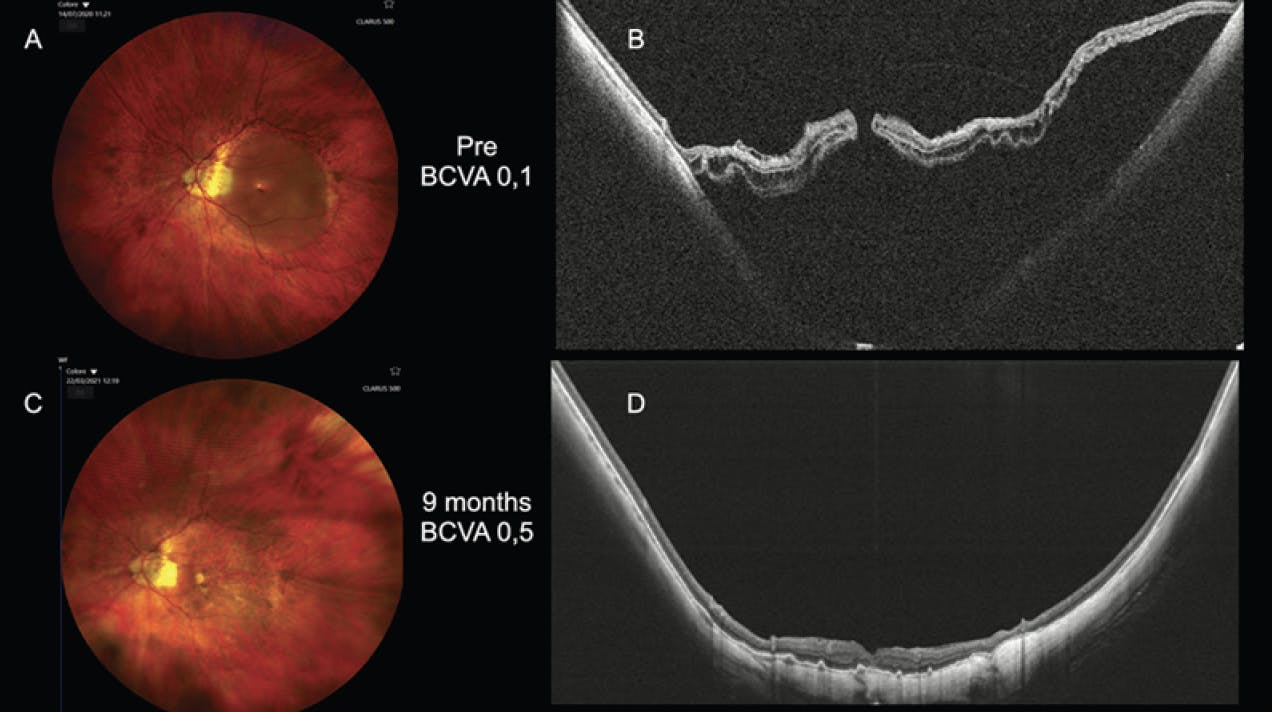

Case No. 1: A 53-year-old female presented with myopic traction maculopathy (MTM) Stage 4C (Figure 1A and B). Her BCVA was 0.05 with a spherical equivalent of -25.0 D and an axial length of 38 mm. The patient underwent a combined pars plana vitrectomy (PPV), macular buckle (MB), and internal limiting membrane (ILM) peel and ILM flap on the associated full-thickness macular hole (FTMH), with SF6 gas injection. Face-down positioning was advised for 3 days postoperatively. One month after surgery, the retina was attached, and the hole was closed (Figure 1C and D). BCVA was 0.2 with a spherical equivalent of -23.0 D. The patient underwent cataract surgery and achieved a final BCVA of 0.6 with a spherical equivalent of -3.0 D at 9 months after surgery.

<p>Figure 1. MTM Stage 4C (A, B). One month after surgery, the patient’s retina was attached, and the hole was closed (C, D).</p>

Figure 1. MTM Stage 4C (A, B). One month after surgery, the patient’s retina was attached, and the hole was closed (C, D).